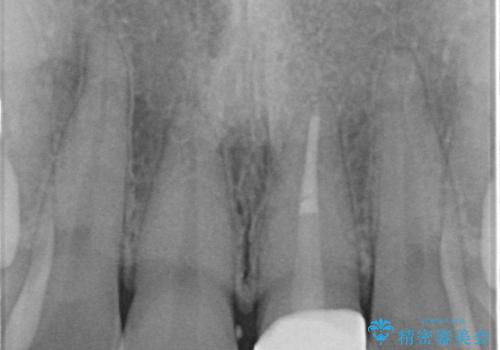

- 前歯の変色とガタつきが気になるとのことで来院された患者様です。

根管治療からやり直しを行った後、ジルコニアクラウンで修復することで、ガタつきと変色の両方を改善していきます。

- 左上1/再根管治療66,000円+ファイバーコア22,000円+仮歯11,000円+ジルコニアクラウン(スタンダード):121,000円 合計209,000円(税込)費用は治療当時の料金となります